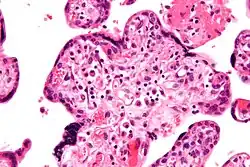

| Micrograph of villitis of unknown etiology, a placental pathology associated with IUGR. H&E stain. | |